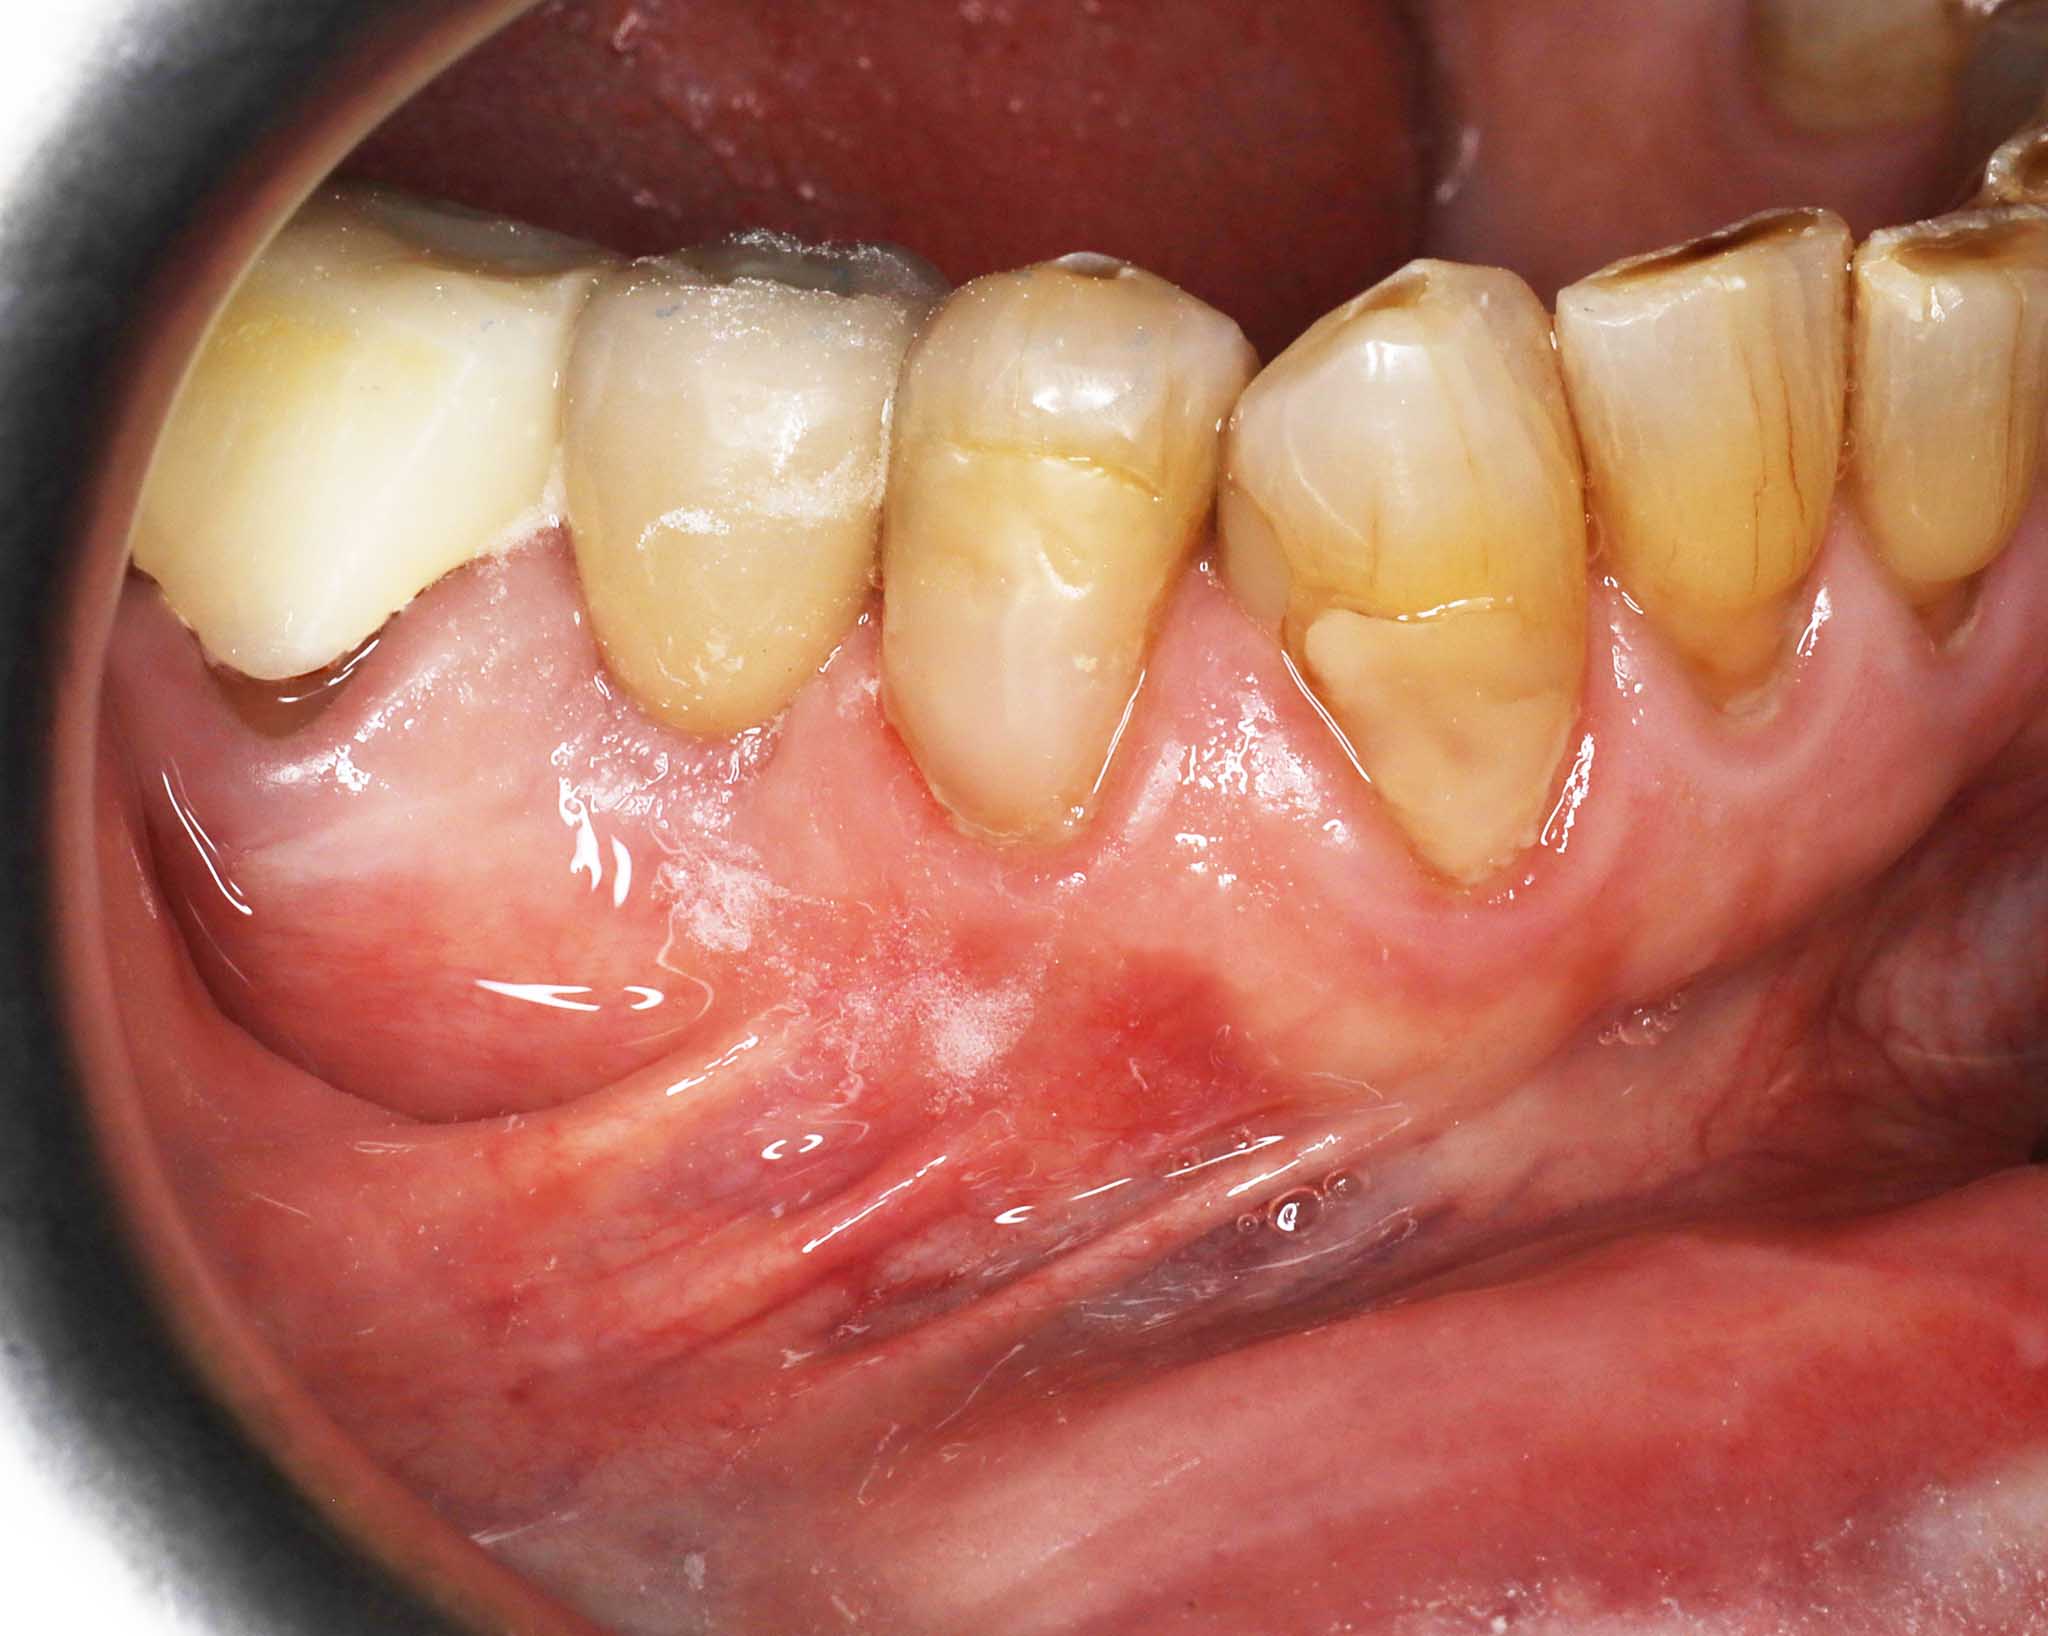

Bildet viser midtre tann som implantat – sammenligning av foto og røntgen.

Før- og etterbilder av tannimplantater – Se våre pasientresultater

Bildet viser resultat før og etter tannimplantat.

Resultat av implantatbehandling dokumentert på foto og røntgen.

Resultat etter tannimplantat.